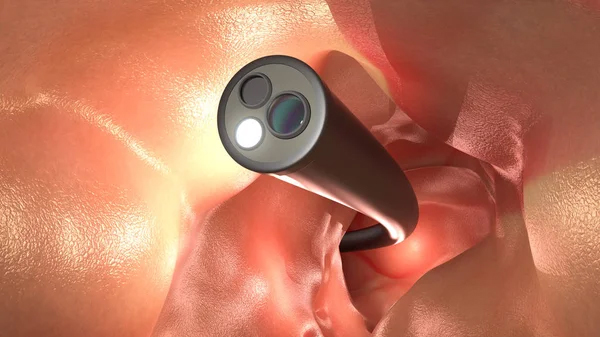

La endoscopia digestiva alta es un procedimiento médico que se utiliza para examinar el esófago, el estómago y la primera parte del intestino delgado, también conocido como duodeno. Durante el procedimiento, se utiliza un endoscopio, un tubo flexible con una cámara y una luz en el extremo, para ver el interior del tracto digestivo en tiempo real.

La endoscopia digestiva alta puede realizarse por diversas razones, como el diagnóstico de trastornos gastrointestinales, como la acidez estomacal, el reflujo gastroesofágico, la úlcera péptica, la inflamación del esófago (esofagitis), la enfermedad celíaca y la enfermedad de Crohn, entre otros. Además, también se puede utilizar para tomar muestras de tejido (biopsias) o para realizar tratamientos, como la eliminación de pólipos o la detección y tratamiento de sangrado.

El procedimiento es generalmente seguro y se realiza bajo sedación para reducir la incomodidad y la ansiedad del paciente. Después del procedimiento, el paciente puede experimentar una leve incomodidad en la garganta y el estómago, pero en general puede retomar sus actividades normales poco después del procedimiento.

En resumen, la endoscopia digestiva alta es un procedimiento médico que se utiliza para examinar el esófago, el estómago y el duodeno para diagnosticar trastornos gastrointestinales y tomar muestras de tejido o realizar tratamientos. El procedimiento es seguro y generalmente se realiza bajo sedación para reducir la incomodidad del paciente.